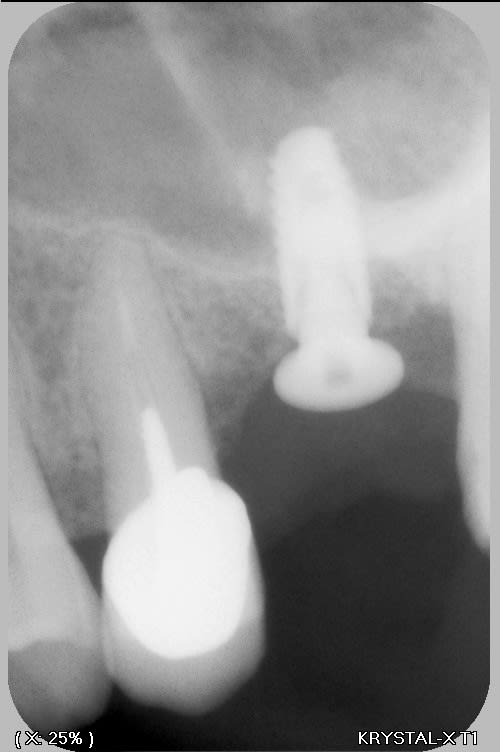

Je trouve que c’est assez flagrant que les implants sont trop vestibulaires….

Une grosse crête gingivale ne veut pas dire grosse crête osseuse